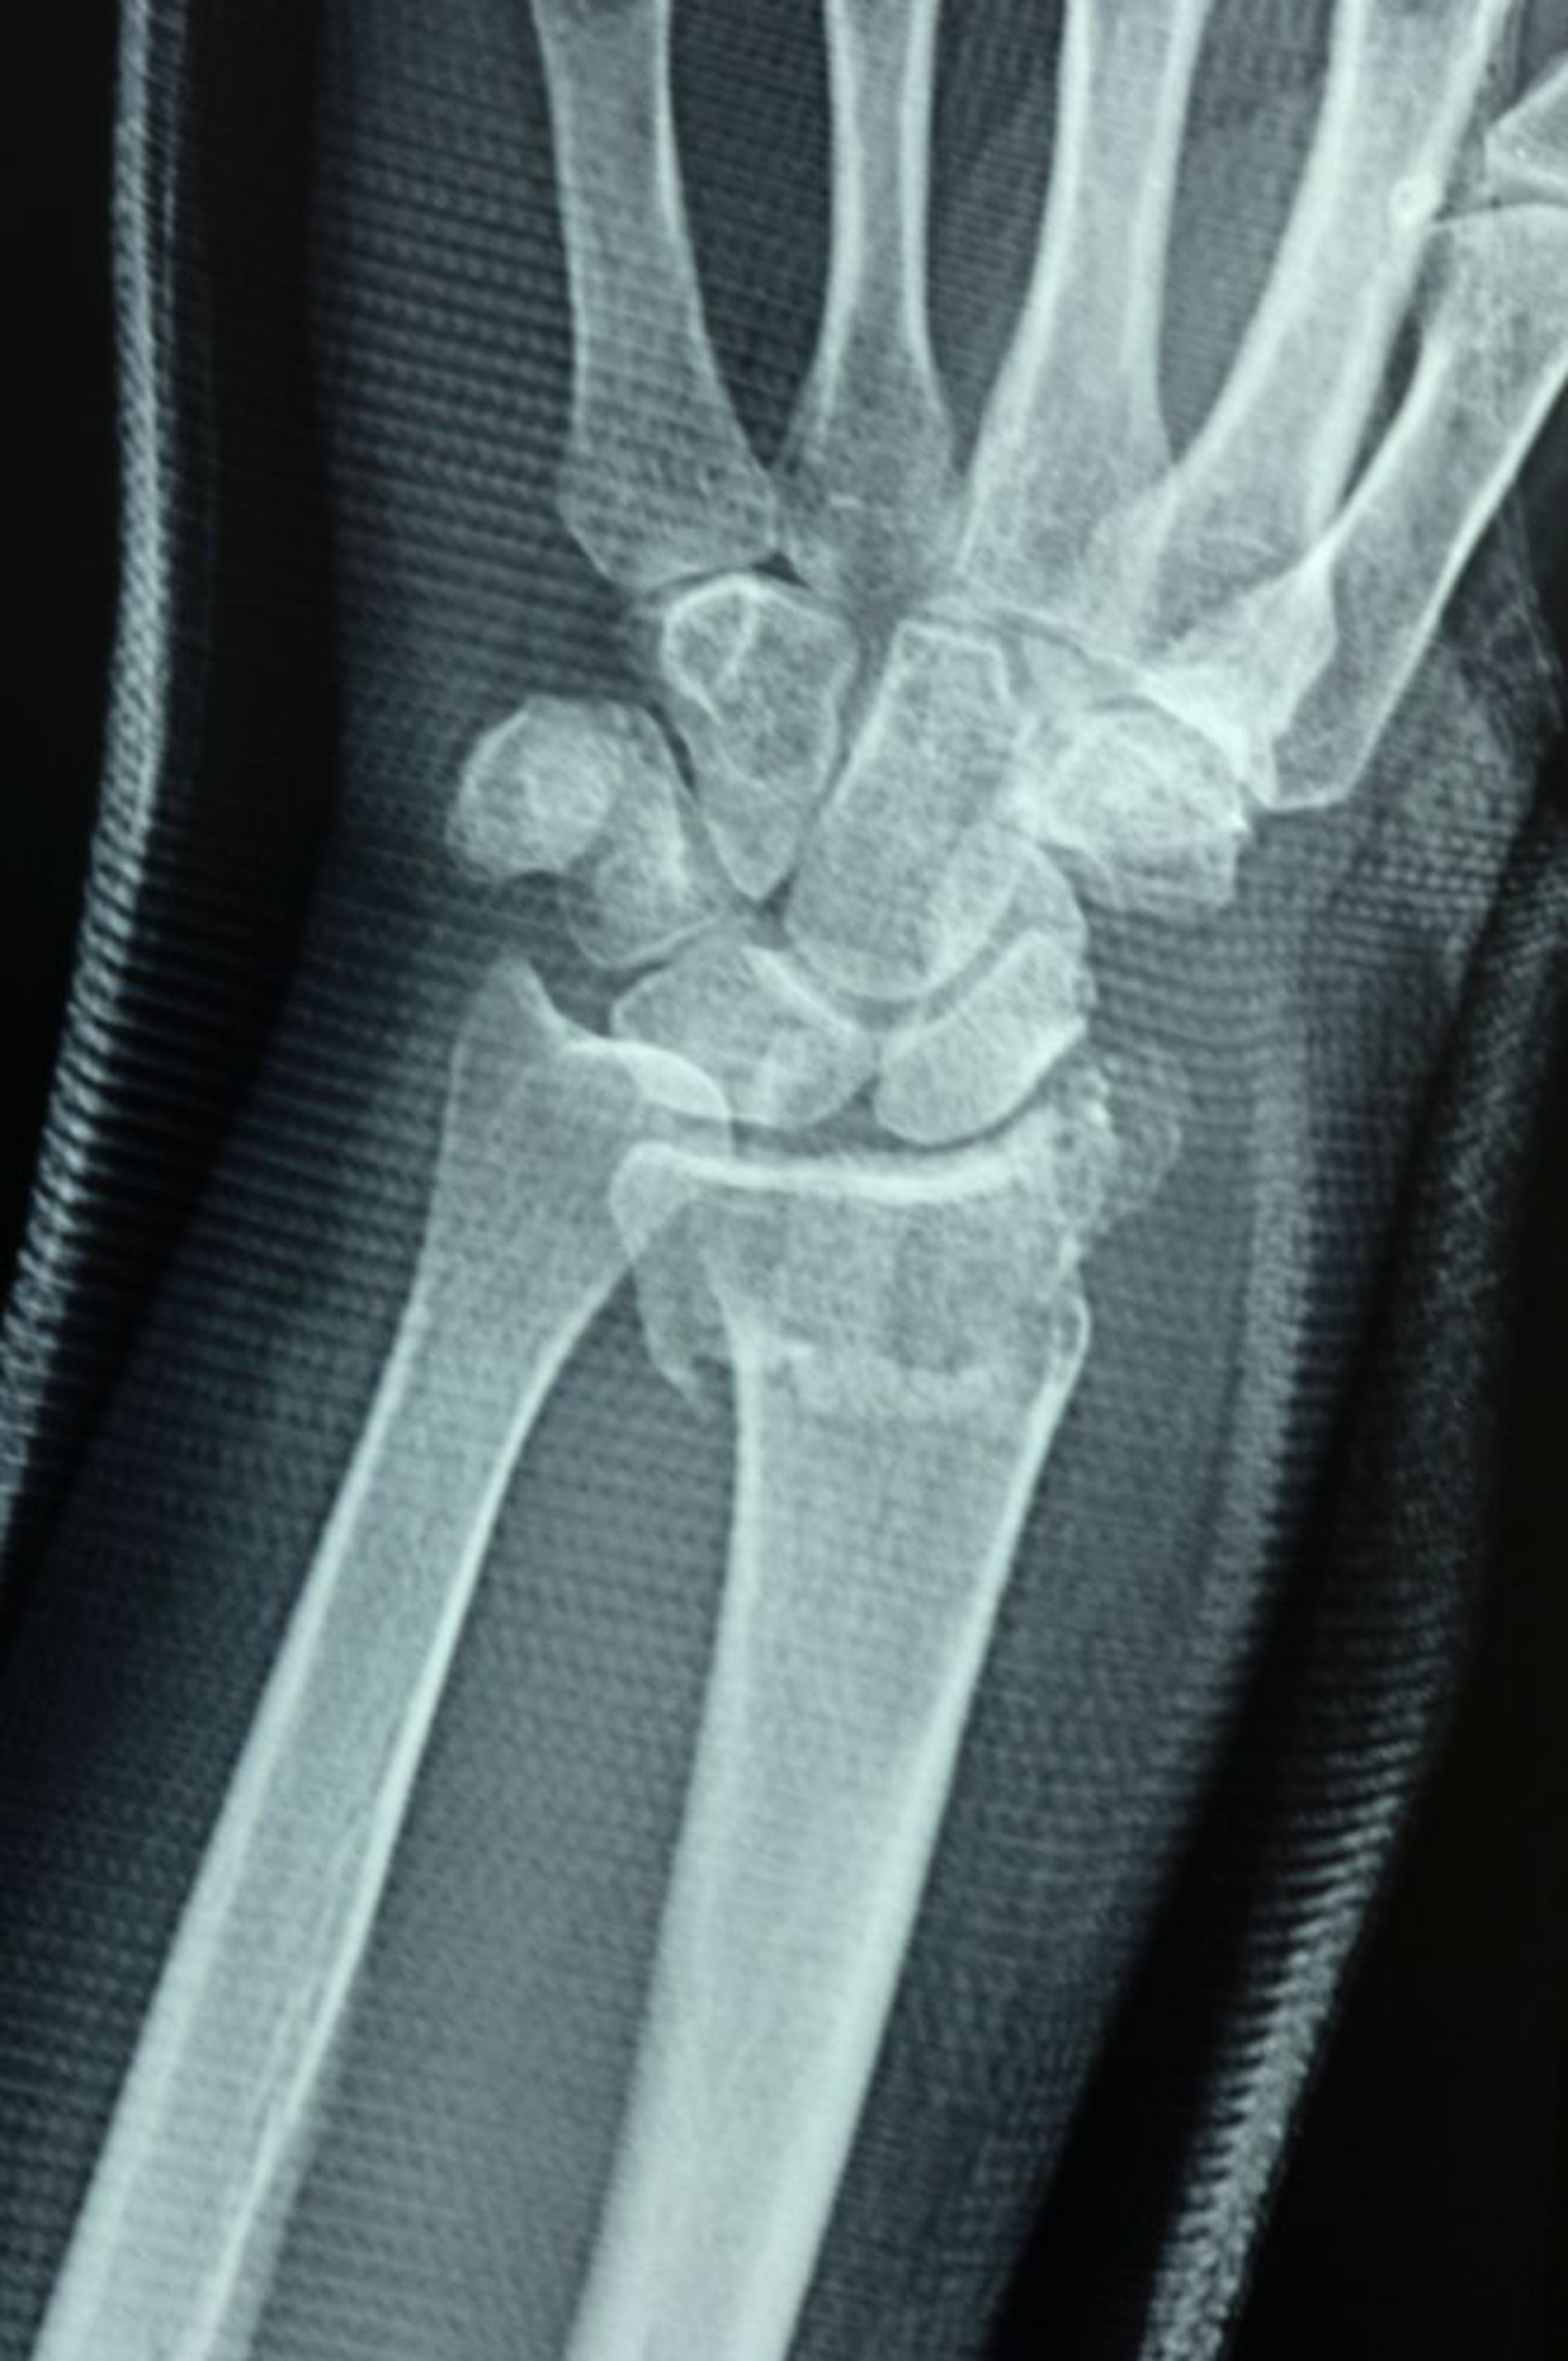

Перелом дистального отдела лучевой кости

Лучелоктевой сустав разрушен, о чем свидетельствует невозможность выравнивания суставных поверхностей дистального отдела лучевой кости и дистального отдела локтевой кости, что приводит к смещению.